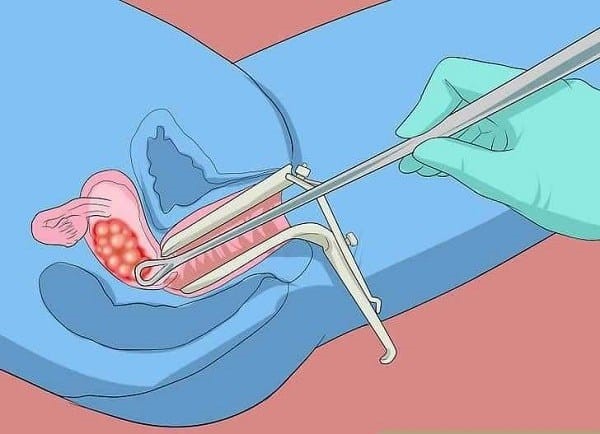

Để chẩn đoán, các bác sĩ sẽ thực hiện siêu âm và nồng độ HCG. Tỷ lệ chính xác của việc chẩn đoán này lên đến 90%. Và để có thể đưa ra những chẩn đoán chính xác, cần phải căn cứ vào giải phẫu bệnh lý, có nghĩa là nạo hay hút lấy mô trong lòng tử cung đi thử.

Trên thực tế, sản phụ có thể điều trị hiện tượng chửa trứng toàn phần. Phương pháp điều trị phổ biến nhất là nong cổ tử cung để nạo, hút sạch thai trứng ra khỏi tử cung. Việc này nên thực hiện sớm để tránh phát triển thành u ác tính hay bị sảy thai.

Sau khi được loại bỏ, sản phụ vẫn tiếp tục được theo dõi và xét nghiệm nồng độ HCG. Thời gian theo dõi khoảng 6 tháng, và trong thời gian này không nên có thai. Nếu sau 6 tháng nạo thai trứng bán phần, nồng độ HCG giảm tốt và ổn định thì có thể có thai lại.

Để đảm bảo an toàn cũng như xử lý kịp thời những biến chứng, sau khi thực hiện nạo hút thai trứng, các mẫu mô cần được xét nghiệm giải phẫu để xác định thai trứng lành tính hay ác tính.

Sau nạo hút thai trứng, các mẫu mô đều được gửi xét nghiệm giải phẫu bệnh lý nhằm xác định xem thai trứng lành tính hay ác tính.

Nếu từ sau thời điểm nạo thai trứng bán phần, nồng độ HCG xuống âm tính, sản phụ sẽ được chỉ định lượng nồng độ HCG mỗi tuần.